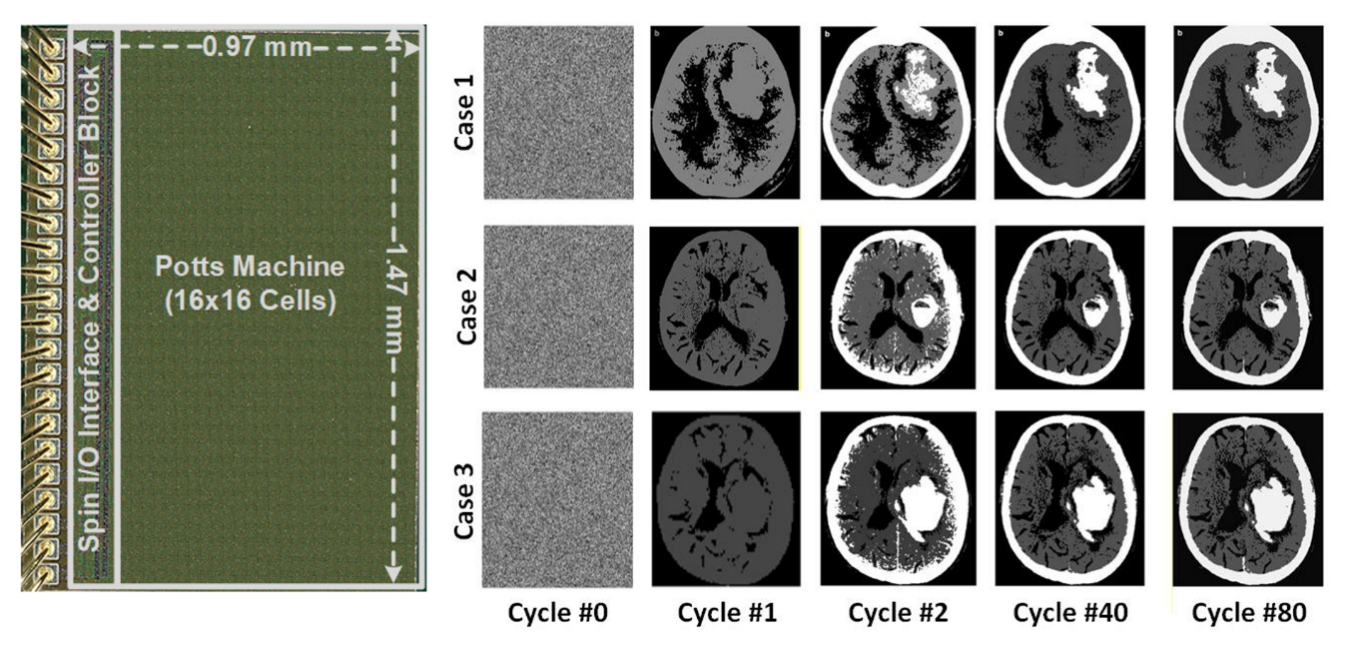

为攻克这一难题,我校半导体学院陈卓俊教授团队成功研发出面向复杂组合优化问题的全集成波茨机处理器芯片。该芯片基于65nm CMOS工艺制造,集成256个自旋单元,支持2至4比特耦合系数位宽及King’s Graph自旋网络拓扑,单个自旋面积仅为4400 μm²。芯片已在CT图像聚类、合金相变模拟等实际应用中完成验证,展现出优越的面积效率与能效表现。

波茨机芯片的显微图及其在CT图像聚类中的应用。